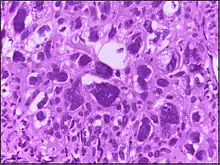

![]() | Tumor giant cell | Malignant neoplasm showing marked anaplasia. Note the marked nuclear pleomorphism, bizarre cells and tumor giant cells. | Category: Histopathology of giant cell tumors | Giant cell tumor |